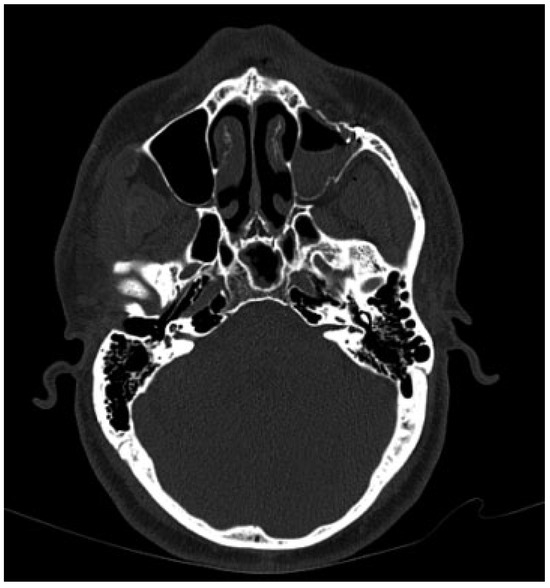

The management of atrophic mandibular fractures in edentulous patients represents an insidious issue for the maxillofacial surgeon due to the biological and biomechanical conditions that are unfavorable for fracture fixation and bone healing. The pur...